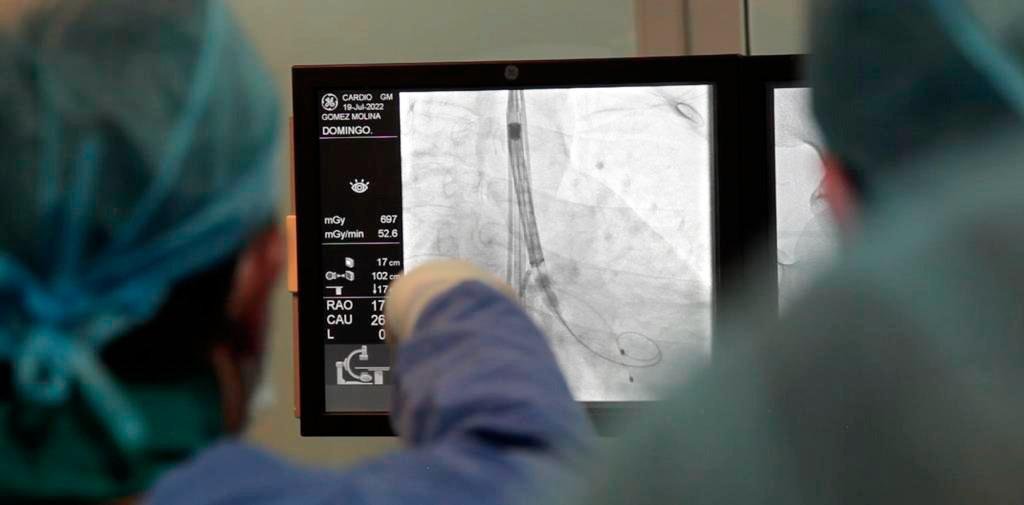

El funcionario estatal destacó que a la fecha se han realizado de manera exitosa tres intervenciones de implante de válvula aórtica con técnica percutánea, a cargo de especialistas en cardiología del Hospital General “Dr. Jesús Gilberto Gómez Maza”, lo que significa un avance en la cobertura de servicios al tratarse de un procedimiento de alta especialidad.

Expuso que la operación consiste en un pequeño corte en la pierna derecha del paciente, donde se introduce un interruptor para colocar la válvula, sin necesidad de cirugía del tórax ni anestesia general y sin intubación.